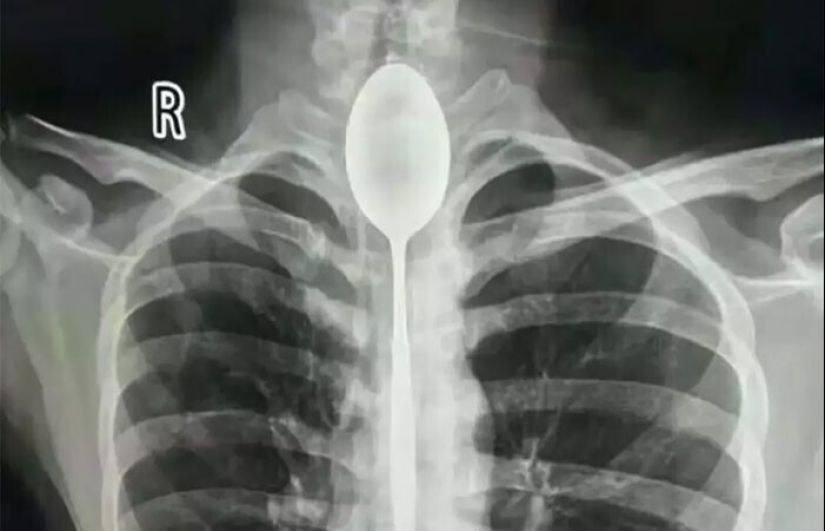

China pasó un año con una cuchara en el esófago. Sorprendentemente, él no tiene inconveniente